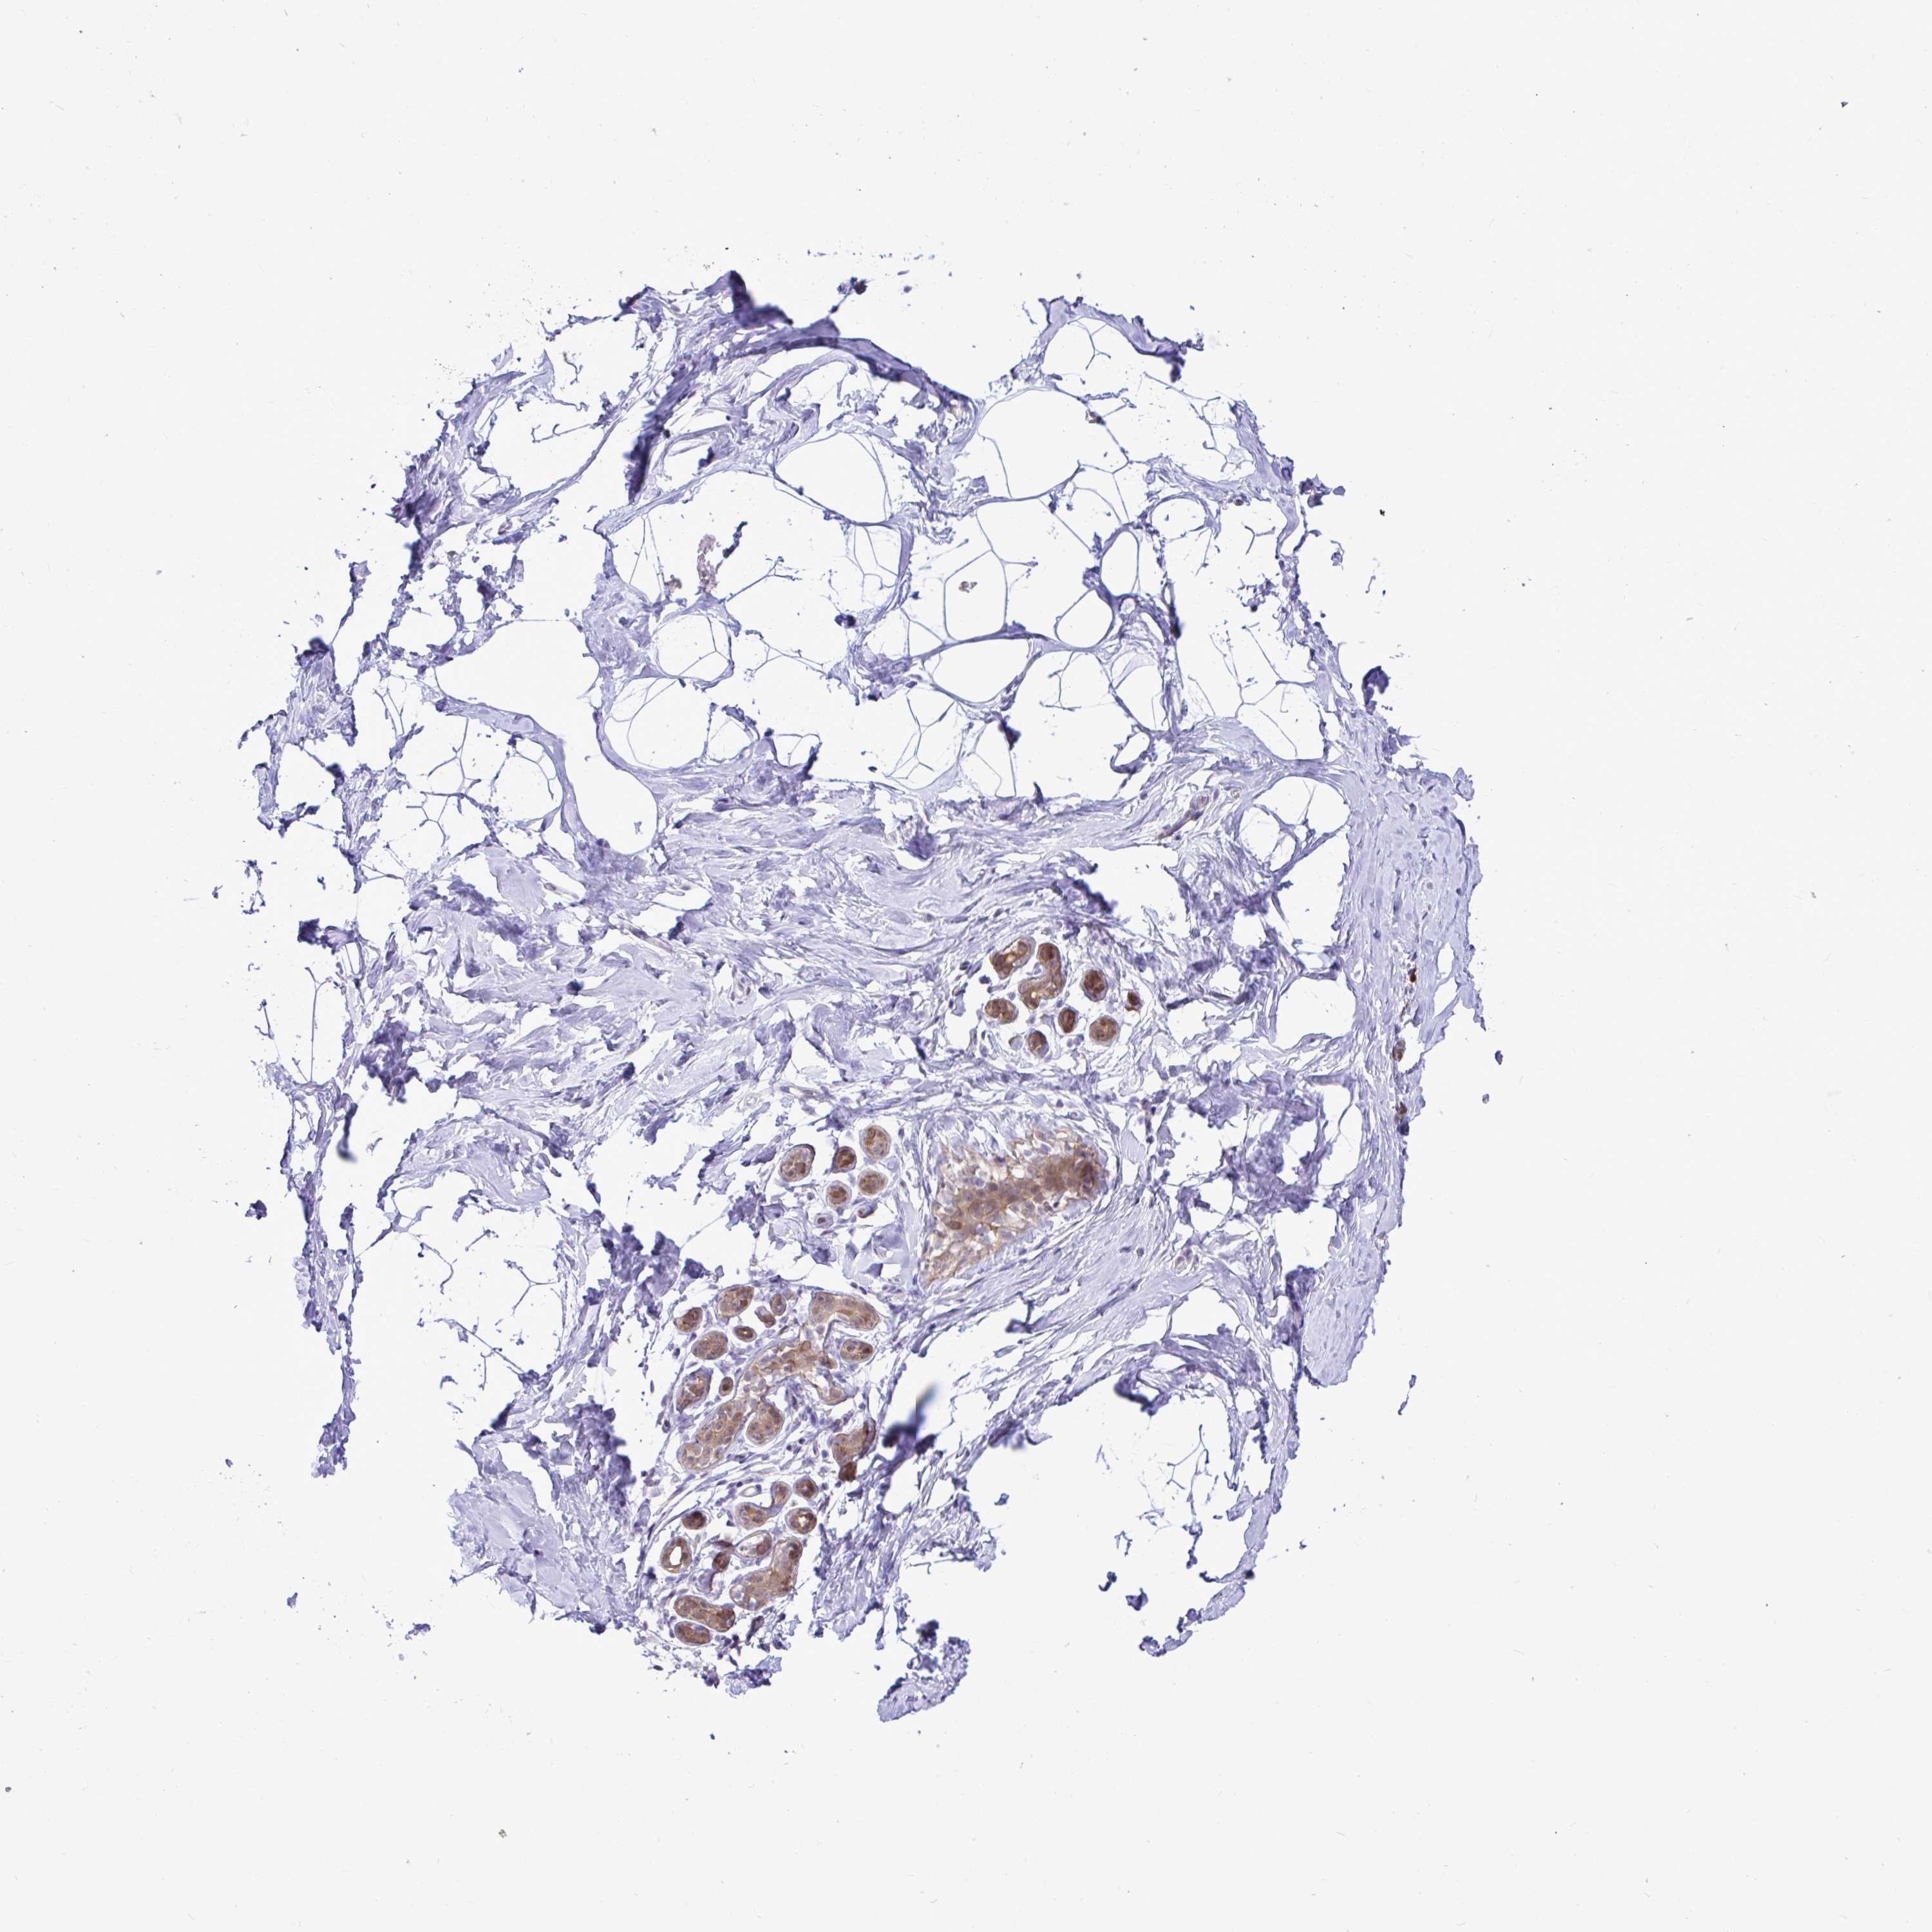

BREAST - Antibody stainingi

Antibody staining in the annotated cell types in the current human tissue is reported as not detected, low, medium, or high, based on conventional immunohistochemistry profiling in selected tissues. This score is based on the combination of the staining intensity and fraction of stained cells.

Each image is clickable and will lead to virtual microscopy that enables deeper exploration of all samples and also displays staining intensity scores, fraction scores and subcellular localization as well as patient and tissue information for each sample.

Antibody HPA059356

Adipocytes Not detected

Glandular cells Low

Myoepithelial cells Not detected